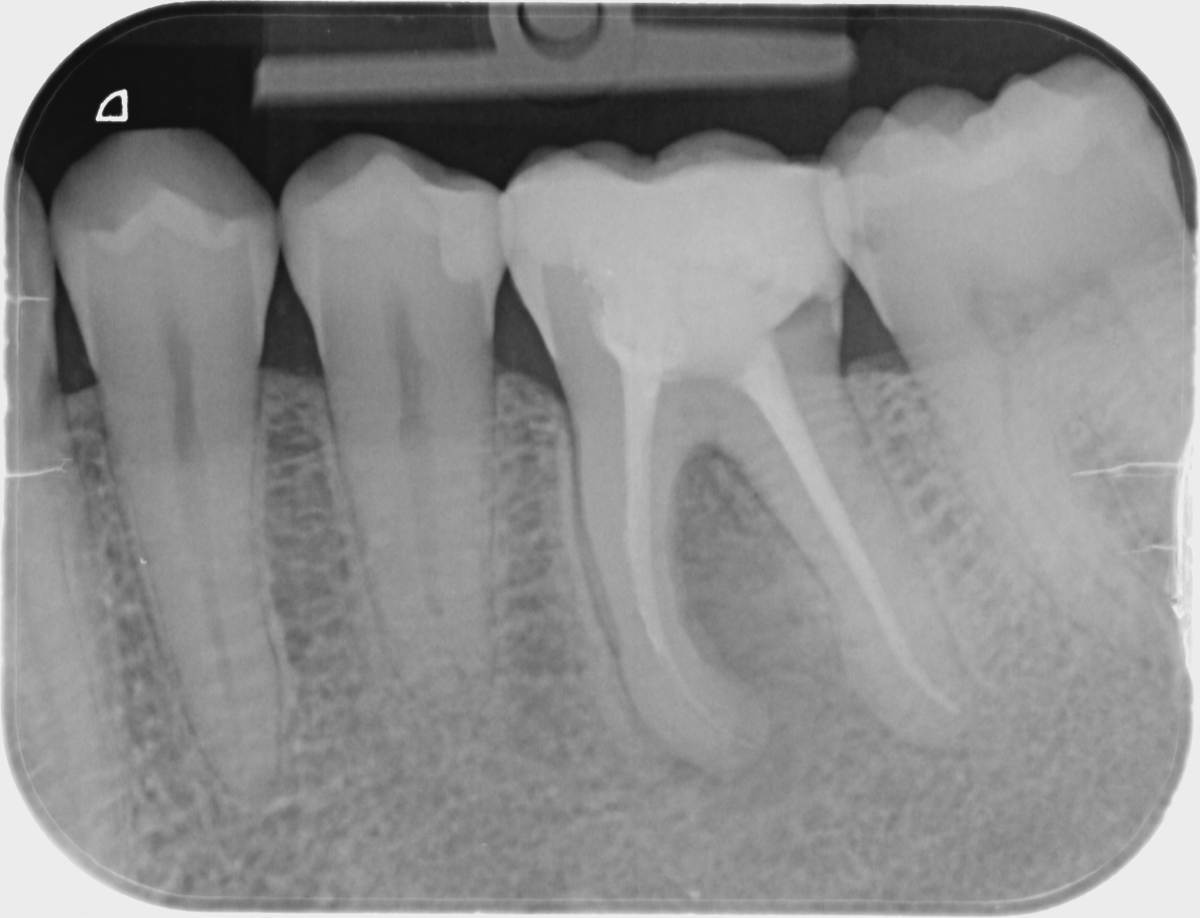

Здравствуйте! Вчера стоматолог сказал, что этот зуб нужно удалить так как в нем трещина. Очень хочу получить еще мнений, так как зуб не беспокоит и стоит крепко. Иногда на десне выступает фистула, потом проходит, но не беспокоит. Я понимаю, что это значит воспаление, но может быть как-то можно сохранить зуб или часть зуба и поставить коронку?

Очень пугает остаться без этого зуба...

Здравствуйте, на представленном снимке трещину или следствие трещины не вижу. По снимку периодонтит. Для ответа нужен очный осмотр, Кт, и возможно удаление пломбы.